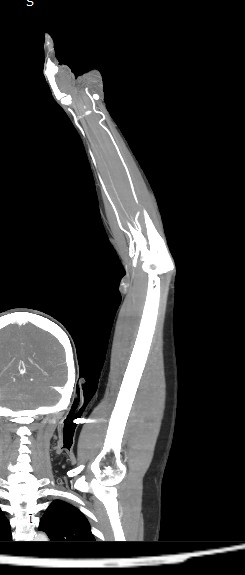

Мультиспиральная компьютерная томография является современным лучевым методом исследования, который позволяет с помощью рентгеновского излучения получить посрезовые снимки и после цифровой обработки создать объемные модели исследуемой области в мельчайших подробностях. Рентгеновские лучи в большей степени поглощаются плотными тканями организма, поэтому на снимках хорошо визуализируются кости скелета. Для оценки состояния мягкотканных структур в обязательном порядке проводится контрастное усиление.

Введение контраста требуется для лучшей визуализации мягких тканей конечностей, включая мышцы, связки, лимфатические узлы, нервные стволы и сосудистую систему и назначается для выявления воспалительных процессов, сосудистой патологии, при подозрении на опухолевые образования.

Йодсодержащий контрастный препарат вводится внутривенно, после чего он хорошо окрашивает кровеносные сосуды. Так как патологические очаги, и особенно опухолевые образования, имеют развитую сосудистую сеть, за счет этого они отчетливо контрастируют на фоне здоровых тканей. Методика контрастирования позволяет проводить точную и достоверную диагностику патологических процессов мягких тканей конечностей, включая опухоли на ранних стадиях развития, когда значительно выше шансы пациента получить эффективное лечение.

В наших медицинских центрах КТ верхней конечности с контрастом выполняется на современных мультиспиральных компьютерных томографах экспертного уровня TOSHIBA AQUILION. Аппараты послойно сканируют область исследования, одномоментно выполняя множество тончайших срезов. В результате получаются снимки высокого качества и трехмерные модели с изображением костного скелета и мягких тканей конечностей. При этом методика скоростного мультисрезового сканирования обеспечивает минимальную дозу рентгеновского облучения для пациента.